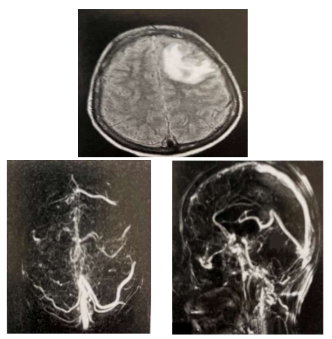

Paciente do sexo feminino, 53 anos, auxiliar de serviços gerais, tabagista 30 anos-maço, hipertensa em tratamento irregular, apresentou cefaleia súbita holocraniana ao ir trabalhar. Foi levada, de imediato, ao hospital referência mais próximo. Na admissão, chegou com abertura ocular e com movimentos de flexão normal ao estímulo doloroso da região glabelar e resposta verbal com frases completas e desconexas da realidade. Anisocoria – esquerda maior que direita e pupila esquerda não ofotoreagente. Apresentava-se com rigidez nucal e sinal de Brudizinski. Foi realizado estabilização imediata e exames de imagem.

Ressonância Magnética do Crânio – T2 Flair e Angioressonância Magnética venosa do Crânio

Assinale a alternativa CORRETA que representa o diagnóstico para o caso acima e seu tratamento correspondente, respectivamente.